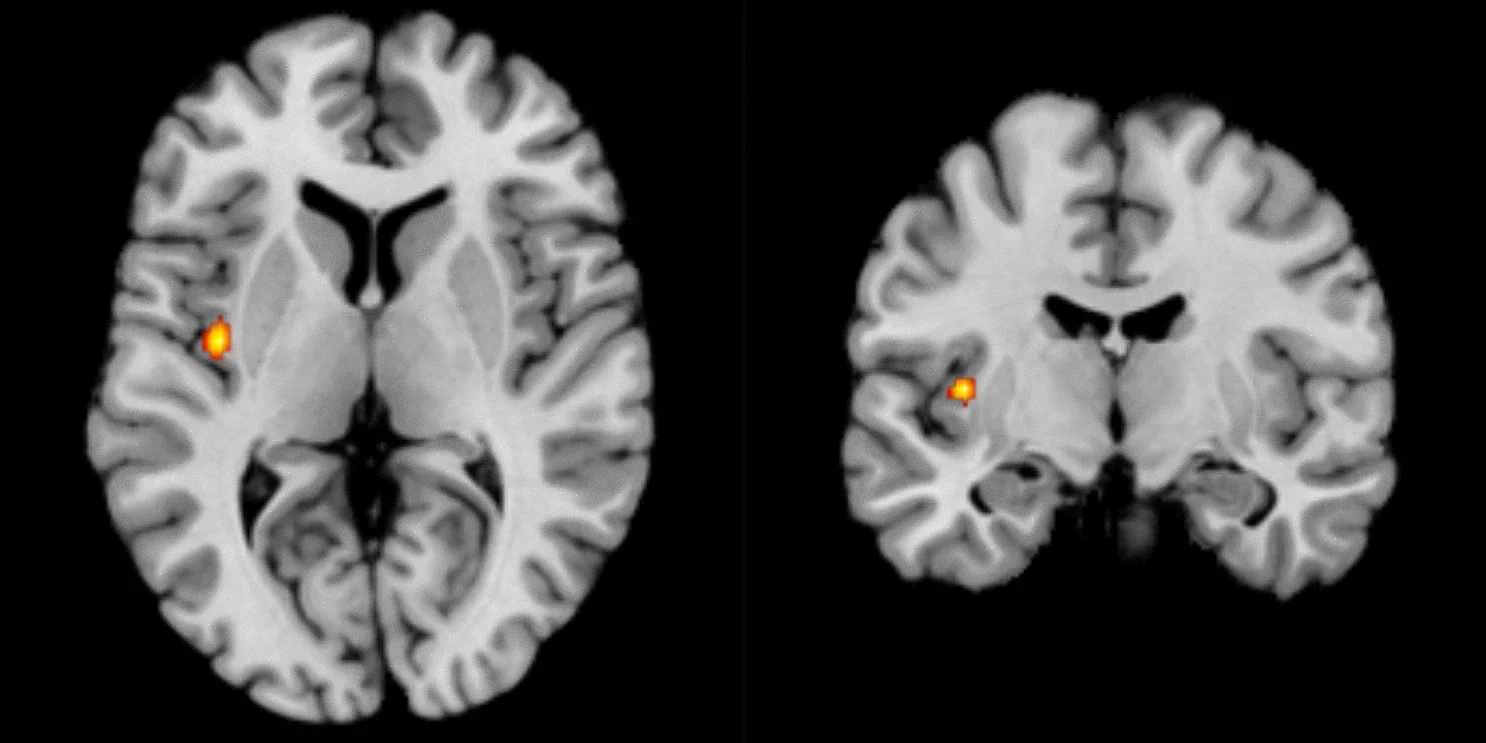

Resonancia magnética de un cerebro humano en la que se aprecia la ínsula activa. Cortesía: Scientific Report

El resultado fue claro. En la corteza insular, una zona ya conocida como centro gustativo primario, aparecían patrones de actividad casi idénticos cuando el estímulo era el sabor o el olor correspondiente.

En términos sencillos: la misma región que se activa al detectar dulce en la lengua se enciende cuando percibimos el aroma dulce retronasal, aunque no haya azúcar presente.

Lo más revelador del trabajo fue comprobar que la confusión entre olores y sabores no ocurre en la parte más básica de la ínsula, encargada de procesar el gusto puro, sino en áreas más complejas de esta región cerebral, que funcionan como un centro de integración y combinan ambas señales. Estas regiones funcionan como un hub donde confluyen las señales de la lengua y de la nariz para dar lugar al percepto final de sabor.

Aunque la insula fue la protagonista, Khorisantono y Seubert detectaron también huellas en otras regiones, como la corteza orbitofrontal lateral (OFC) y el lóbulo parietal inferior. Sin embargo, la insula fue la única corteza quimiosensorial primaria en mostrar esta integración, lo que la convierte en candidata a nodo central del sabor.